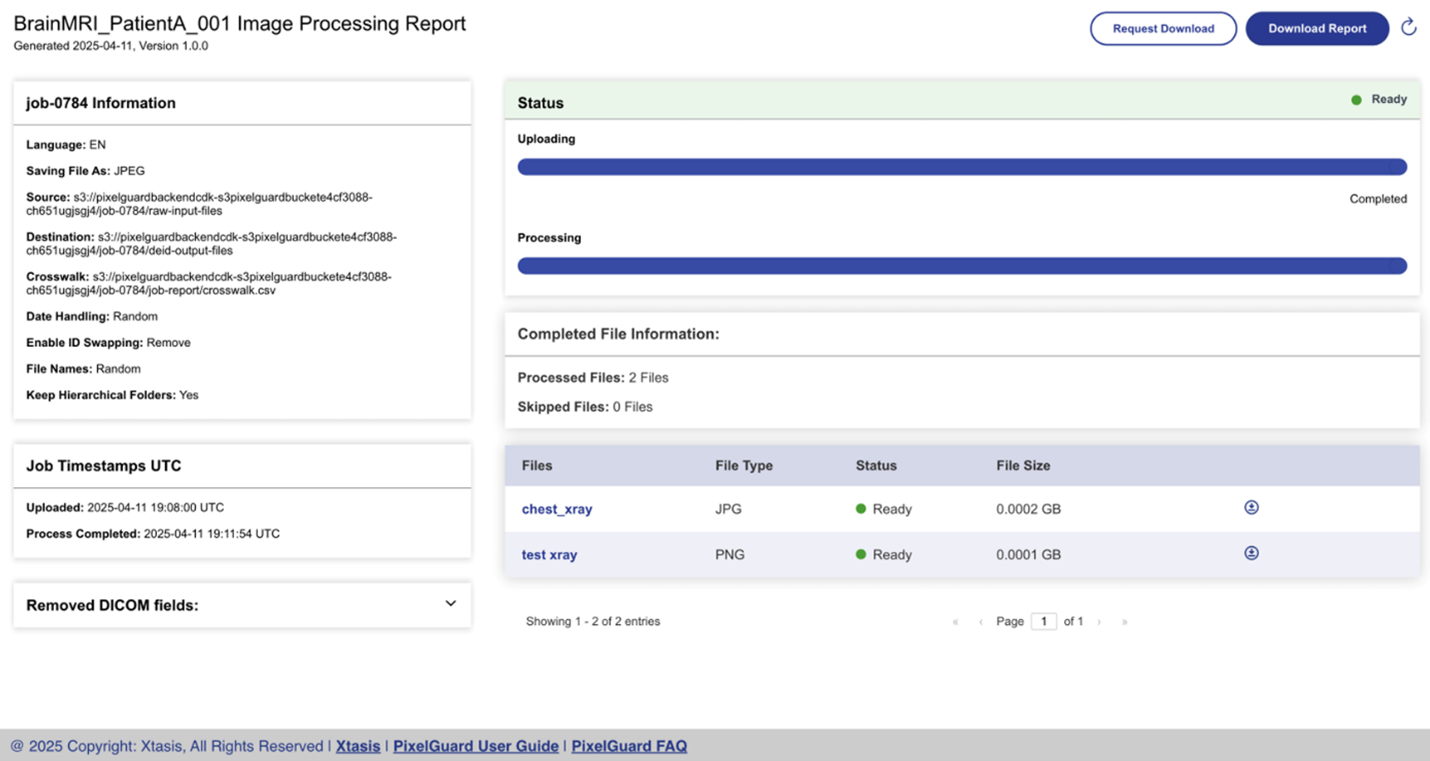

PixelGuard—built on Amazon Web Services (AWS) and created by Northwestern University Assistant Professor and Founder of Xtasis, LLC, Dr. Adrienne Kline—is an advanced software solution that deidentifies medical images while preserving clinical relevance and efficacy. It uses over 75 state-of-the-art AI-driven models capable of detecting and redacting multilingual, multi-orientation text across all major formats (DICOM, JPEG, PNG, NIfTI, etc.), alongside configurable metadata anonymization. With an intuitive UI, enterprise SSO, and in-tenant deployment (no data egress), PixelGuard delivers secure, compliant, and high-throughput image de-identification. PixelGuard is available on AWS Marketplace. ScaleCapacity—an AWS Partner—was instrumental in the development of the UI, cloud infrastructure, and deployment to AWS Marketplace.

The storage layer identifies the format of an image needing de-identification and based on the specific de-identification configuration, the image metadata defined by the DICOM tags and the Pixel-level de-identification is undertaken. Furthermore, the image can be compressed for storage optimization and a crosswalk file referencing a unique ID is created. The crosswalk file makes it possible to do a reverse lookup of the original file if it is ever needed. Care should be exercised to secure the crosswalk file and store it separate from the de-identified file.

The de-identified storage layer stores the processed de-identified medical image, which can be used by medical researchers as part of a study. Furthermore, the image can be generated in various formats consistent with the needs of the research study.

The de-identified images can be created in conjunction with a crosswalk file that can maintain a mapping between an identifier in the de-identified image and a relevant identifier in the original image. The crosswalk file is maintained separately and encrypted to allow only authorized individuals to trace the de-identified image back to its original source if needed.

The auditing, monitoring, and observability layer stores access logs to make sure that records of who accessed what, when, and how can be stored for record keeping purposes. Furthermore, detailed error logs if any can be stored to enable troubleshooting if certain medical images could not be de-identified.

The following images provide an overview of the image redaction experience using PixelGuard.